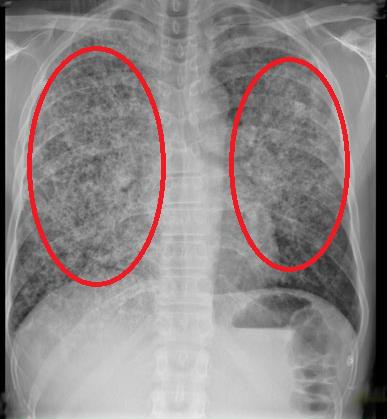

A chest radiograph is performed and is shown in Figure A. Which of the following is the most accurate test to diagnose this patient’s condition?

Figure/Illustration A is a chest radiograph showing bilateral opacities consistent with infiltrates (red circles). These findings can be seen in a patient with Pneumocystis pneumonia.